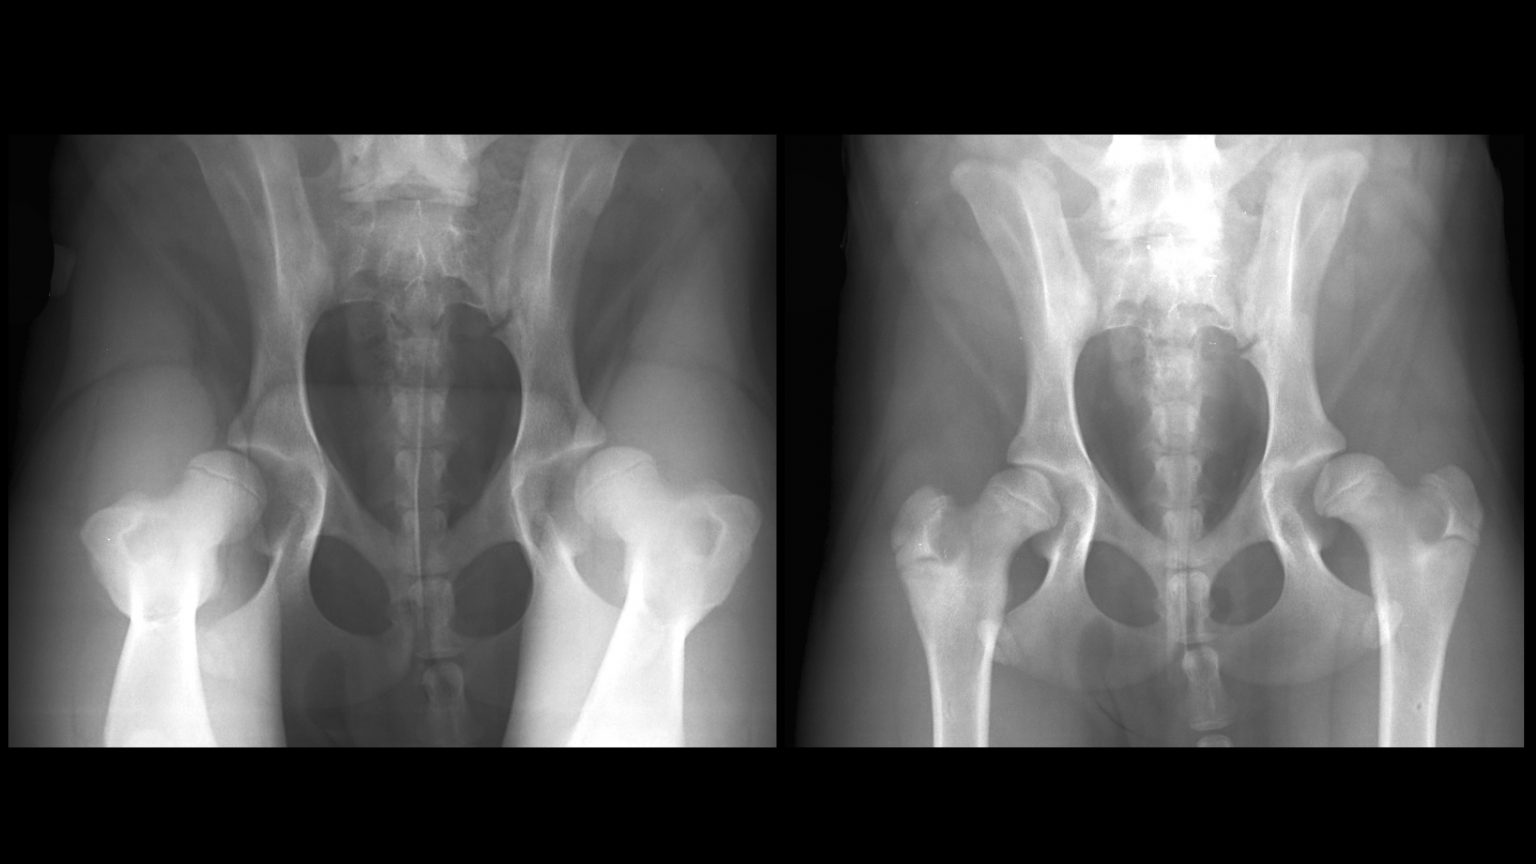

From orthofixar.com

Developmental Dysplasia Of The Hip OrthoFixar 2024 Horse Hip Dysplasia Symptoms Most horses with coxofemoral pathology show some pain on proximal limb flexion or abduction. What are the symptoms of hip dysplasia in horses? Broken bones, whether the pelvis or femur, have more dramatic clinical signs that make diagnosis straightforward. Traumatic hip luxation is painful, impacting weight bearing and. Hip luxation is commonly caused by trauma, but joint degeneration or hip. Horse Hip Dysplasia Symptoms.